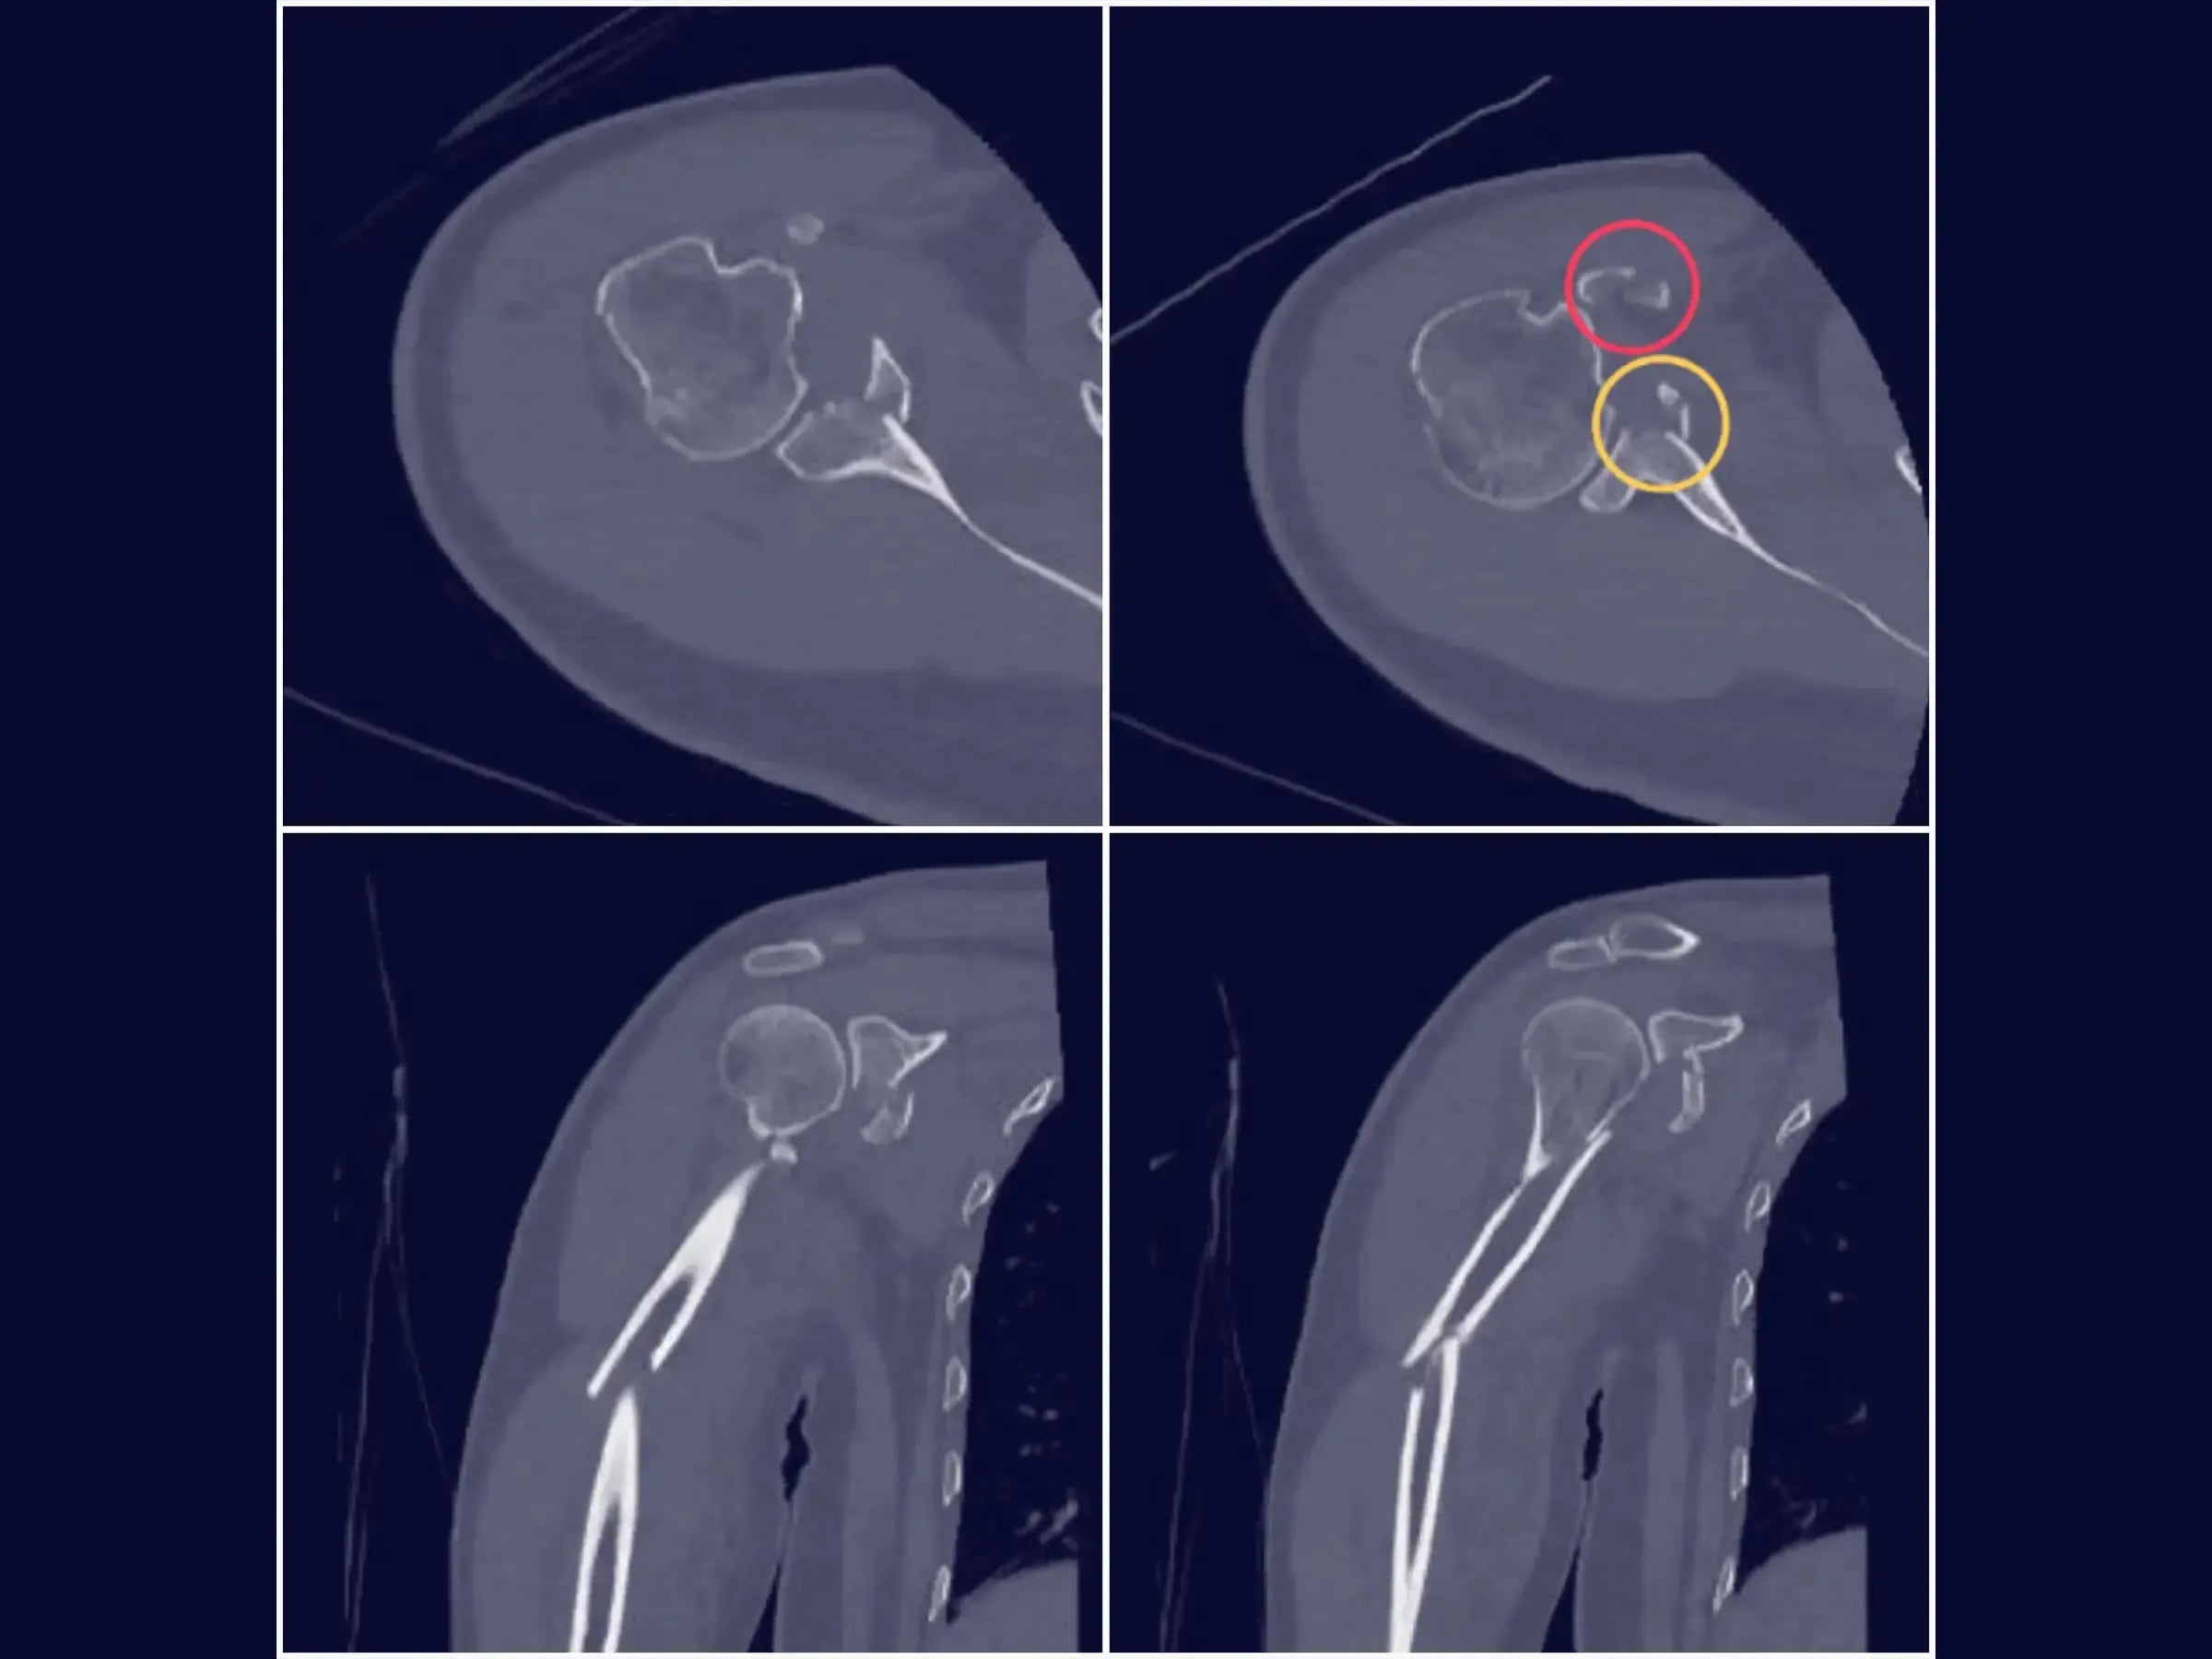

- Osteosíntesis efectiva: demostración de visualización transversal del fragmento y técnica de fijación con tornillos de compresión para la estabilidad de la fractura glenoidea.

- PDF detallado: Este material del curso en PDF describe en detalle el abordaje quirúrgico para la fijación de una fractura glenoidea, incluyendo los pasos de exposición e identificación inicial, separación de la cápsula y el manguito rotador, artrotomía y exposición del reborde glenoideo anterior, visualización y fijación de la fractura, y cierre. El documento también ofrece un resumen práctico del procedimiento, que abarca el acceso, la disección, la artrotomía, la retracción, la visualización y la fijación.